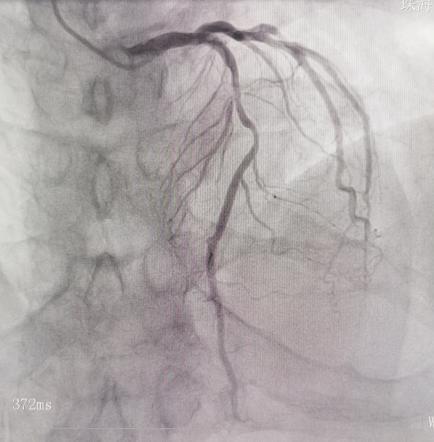

案例1

冠脉造影提示LAD中段75%左右狭窄,FFR检测结果为0.76,小于0.8,提示心肌存在功能性缺血,需要植入支架治疗。